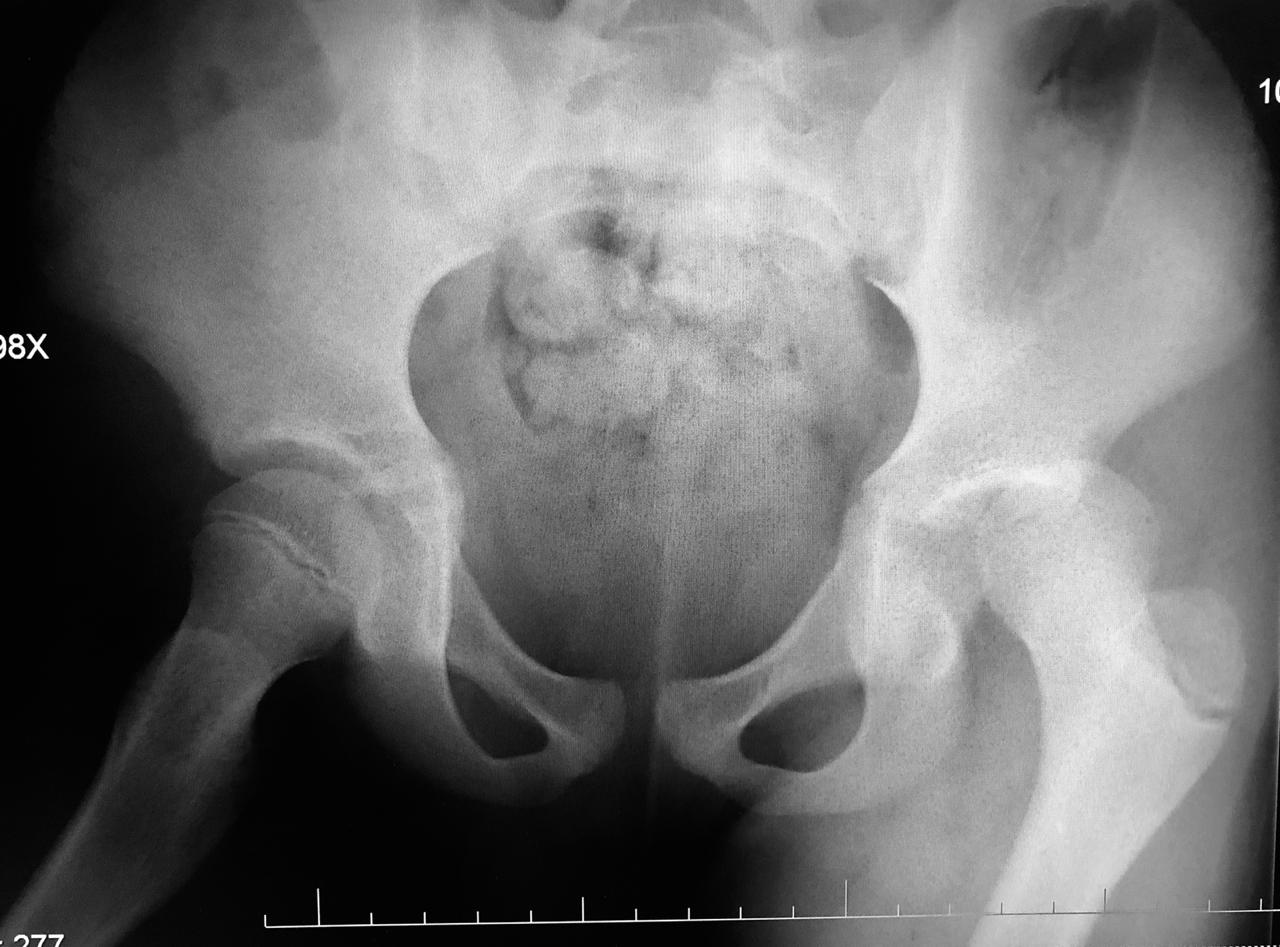

AP radiograph of the pelvis reveals extensive fluffy or "whiskering" enthesopathy of the iliac crests (red arrows), ischial tuberosities (yellow arrows), and the trochanters (black arrows). Note is also made of ossification of the iliolumbar ligament (blue arrow). Importantly, both sacroiliac joints appear normal. These findings are in keeping with diffuse idiopathic skeletal hyperostosis (DISH).

Diffuse Idiopathic skeletal hyperostosis (DISH) is a bone-forming diathesis primarily affecting the spine, with ossification of tendons and ligaments. Most of us are familiar with the spinal findings; however there are extraspinal manifestations as well such as hyperostosis at ligament attachments in the pelvis, calcaneus, tarsal bones, ulnar olecranon and patella.

Usually these are incidental findings without significant morbidity.